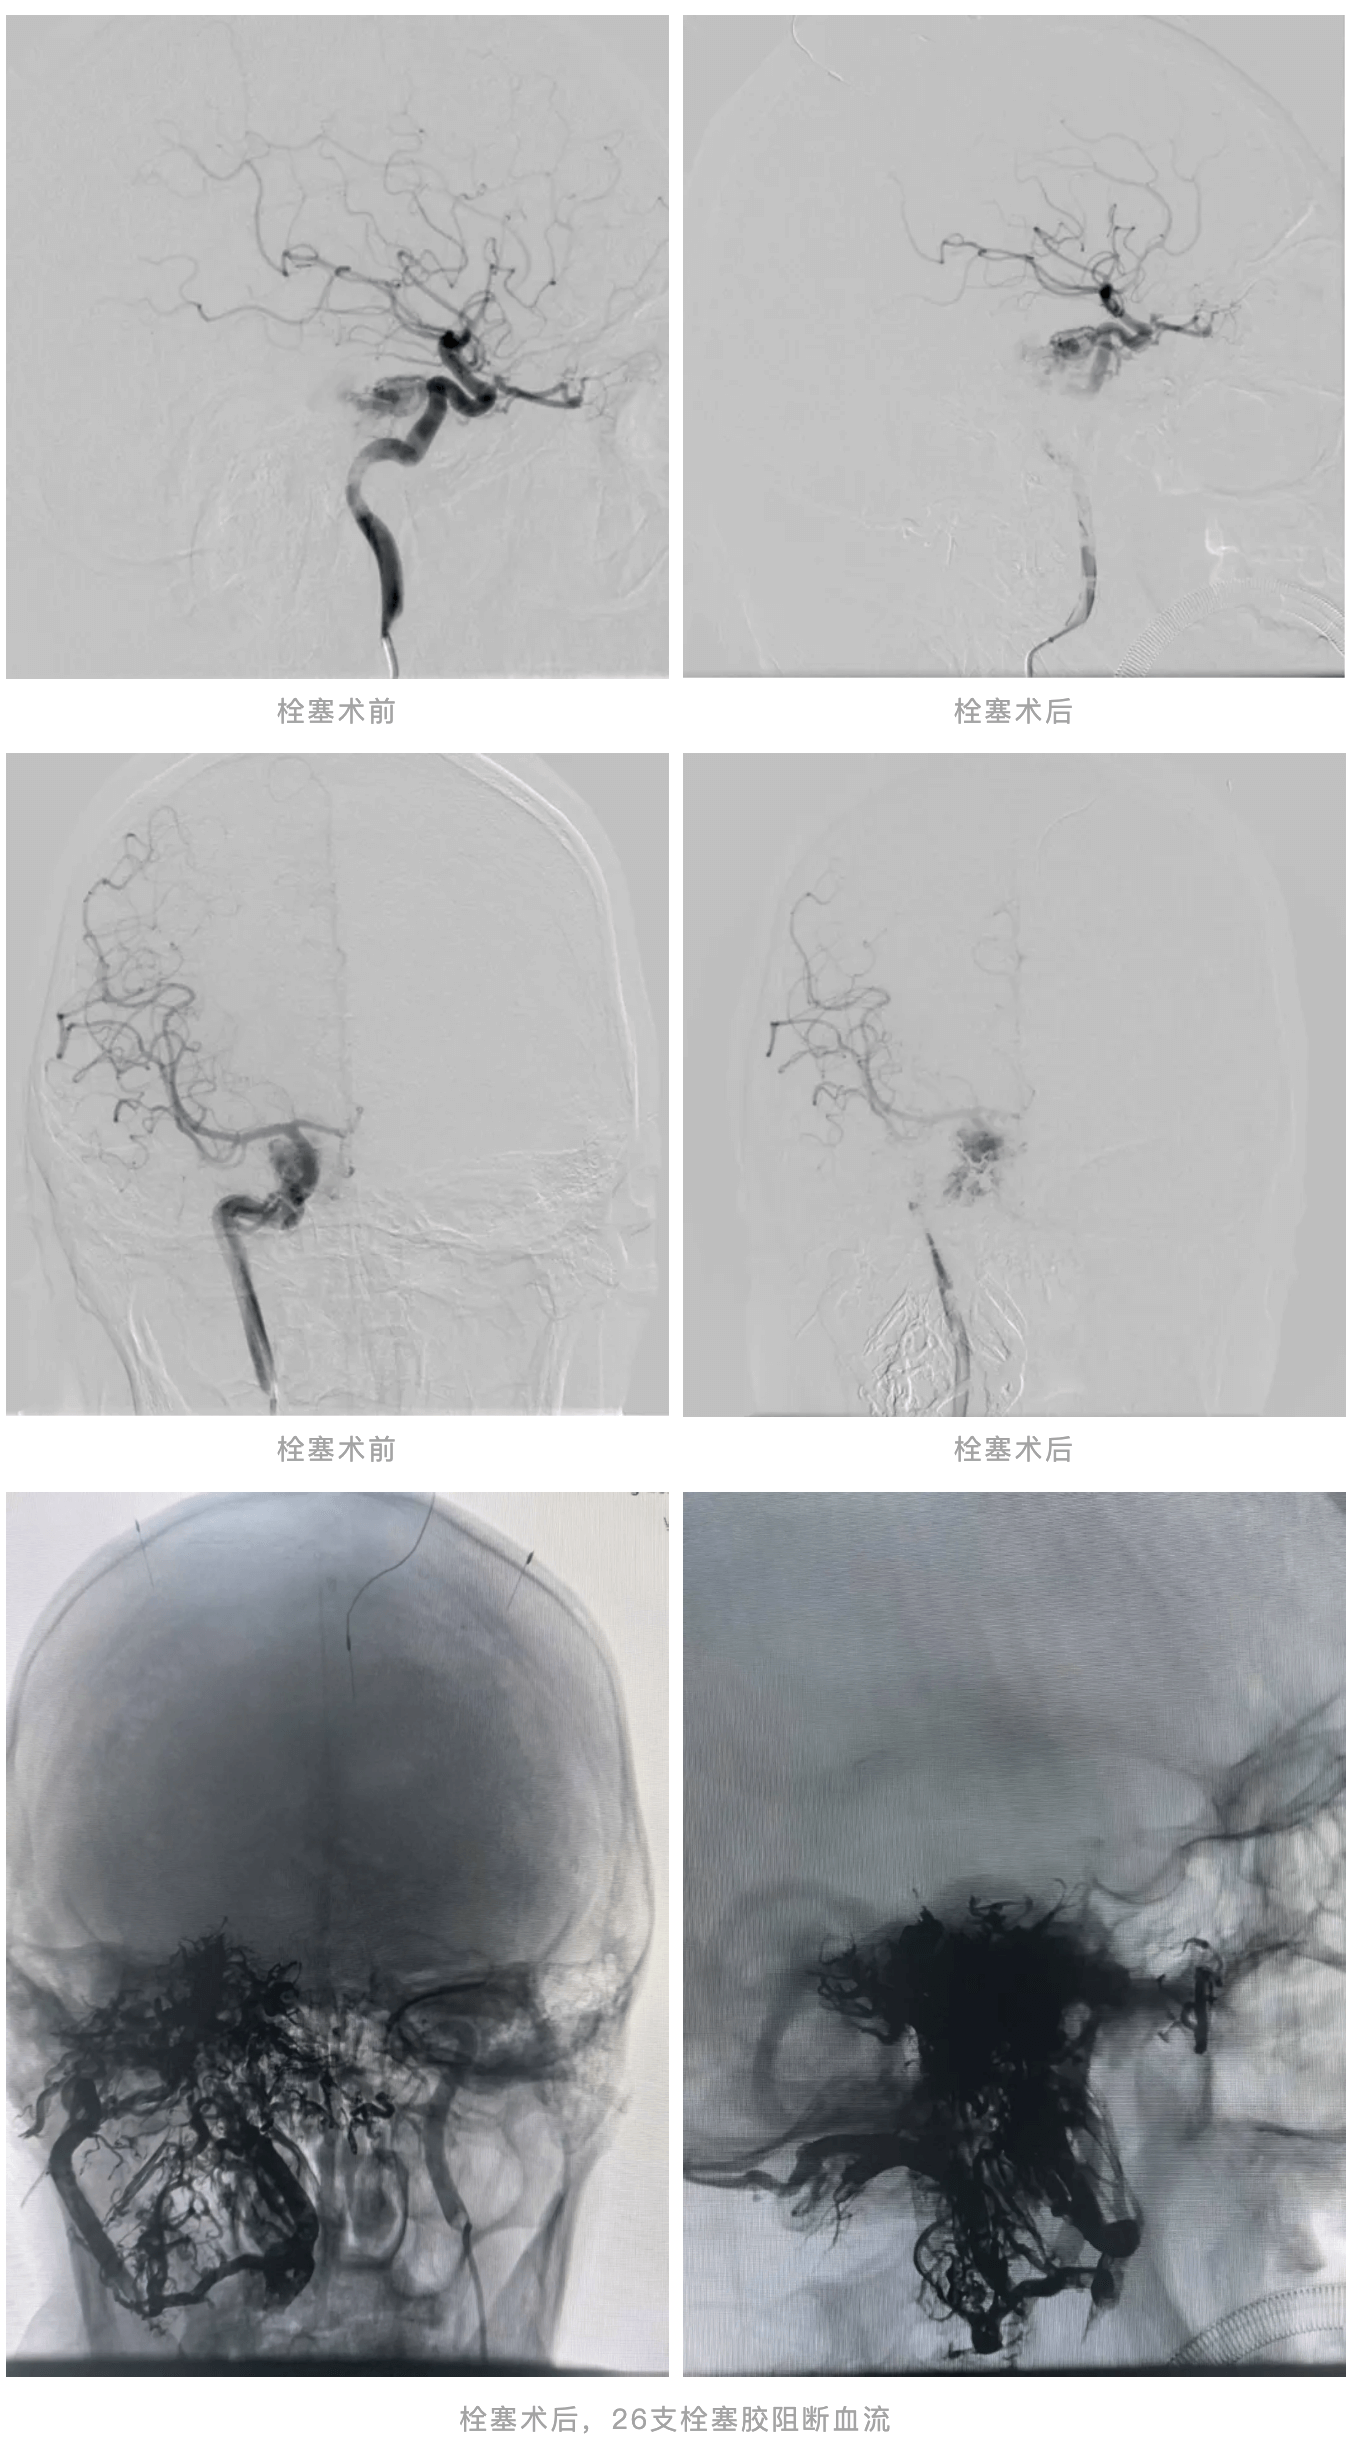

成功的栓塞

是开启肿瘤切除高难度手术的钥匙

第一场颅内血管栓塞术由神经介入团队操刀。盖延廷主任操作微导管精准超选多根肿瘤供血动脉,共注入26支医用栓塞胶阻断血流,这相当于一般性复杂手术用量的6倍!整个手术过程耗时8个小时,需要无比精细的手上感觉和极大的耐心。